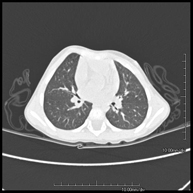

- TC Tòrax

Prova diagnòstica que consisteix en obtenir imatges del tòrax d'alta definició anatòmica (pulmons, cor, mediastí, grans vasos, caixa toràcica, etc. ) mitjançant l'ús d'un equip de TC (Tomografia Computeritzada). Aquestes imatges s'estudien posteriorment en una estació de treball que permet reconstruccions bidimensionals en diferents plànols de l'espai i també reconstruccions 3D (volumètriques). Alguns estudis requereixen l'ús de contrast iodat per millorar la definició de les imatges. - Angio –TC Aorta toràcica

Prova radiològica que consisteix en obtenir imatges del coll d'alta definició anatòmica, mitjançant l'ús d'un equip de TC (Tomografia Computeritzada). - TC Tòrax

Prova diagnòstica que consisteix en obtenir imatges del tòrax d'alta definició anatòmica (pulmons, cor, mediastí, grans vasos, caixa toràcica, etc.) mitjançant l'ús d'un equip de TC (Tomografia Computeritzada). Aquestes imatges s'estudien posteriorment en una estació de treball que permet reconstruccions bidimensionals en diferents plans de l'espai i també reconstruccions tridimensionals (3D: volumètriques). Alguns estudis requereixen l'ús de contrast iodat per millorar la definició de les imatges. - TC Abdomen